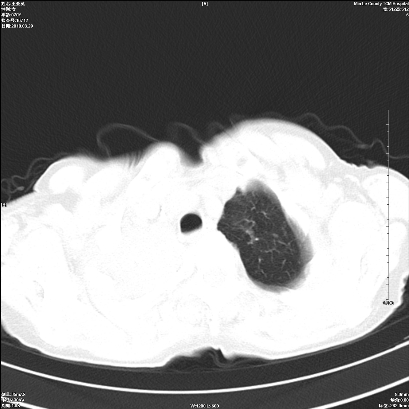

标题: CT25424:女性,70岁,胸闷、咳嗽月余。 [打印本页]

右肺上叶支气管开口阻塞,上叶呈不均匀致密影,右肺中下叶内见斑片状密度增高影,上叶见钙化点,纵隔内见钙化淋巴结,桶状胸,右下肺动脉增粗,残根征,意见:1.右肺中心性肺癌;2.右肺陈旧性结核;3.肺心病。

ct所见:右肺上叶肺不张,呈软组织密度影向肺门区聚拢,其内可见含气段支气管及细支气管影,病灶内尚可见钙化结节。右肺上叶支气管狭窄,段支气管壁可见钙化。右肺下叶背段、右肺中叶见不规则小片絮状影及纤维条索影,形态较僵硬。右肺中叶胸膜旁可见多个小结节影。纵膈内见钙化淋巴结。

分析:右侧胸廓及右肺体积缩小,说明病变时间比较长了,应该是有数年的时间了,如果是短期内出现的肺不张,只会引起纵膈向患侧移位,而不会引起胸廓的塌陷。不张的肺组织内可见含气支气管影,说明右肺上叶支气管没有完全中断,只是狭窄。右肺中叶、下叶散在不规则病灶,部分呈纤维化改变。纵膈内的淋巴结大部分钙化。因此,本例给我的感觉良性病变的可能是大。

结论:考虑右肺上叶支气管内膜结核合并右肺上叶肺不张;右肺中叶、下叶陈旧性肺结核改变。